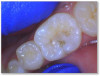

Figure 6a through Figure 6d show a procedure using a bulk fill packable as an interproximal Class 2, without using a bulk fill flow and not done with the snowplow technique to see how well the composite adapted to the margin. A light curable resin-modified calcium silicate liner (Bisco TheraCal LC) was used to perform an indirect pulp cap. A packable bulk fill composite was applied as a single increment layer to successfully restore the tooth. The material (Kerr SimpliShade Bulk Fill Packable) provided good adaptation to the tooth without gaps or polymerization stress lines and demonstrated great polishability and blendability. The patient reported no post operative sensitivity or discomfort in the 9 months after the restoration was performed. Sensitivity can be a concern if a composite is subjected to too much polymerization shrinkage.

Fig 6a. A procedure using a bulk fill packable as an interproximal Class 2, without using a bulk fill flow and not done with the

snowplow technique. A light curable resin-modified calcium silicate liner (Bisco TheraCal LC) was used to perform an indirect pulp cap. A

packable bulk fill composite was applied as a single increment layer. The material (Kerr SimpliShade Bulk Fill Packable) was used to provide

good adaptation to the tooth without gaps or polymerization stress lines and demonstrated great polishability and blendability.

Fig 6a.

Fig 6b. A procedure using a bulk fill packable as an interproximal Class 2, without using a bulk fill flow and not done with the

Fig 6b.

Fig 6a. through 6d. A procedure using a bulk fill packable as an interproximal Class 2, without using a bulk fill flow and not done with the

Fig 6c.

Fig 6d. A procedure using a bulk fill packable as an interproximal Class 2, without using a bulk fill flow and not done with the

Fig 6d.